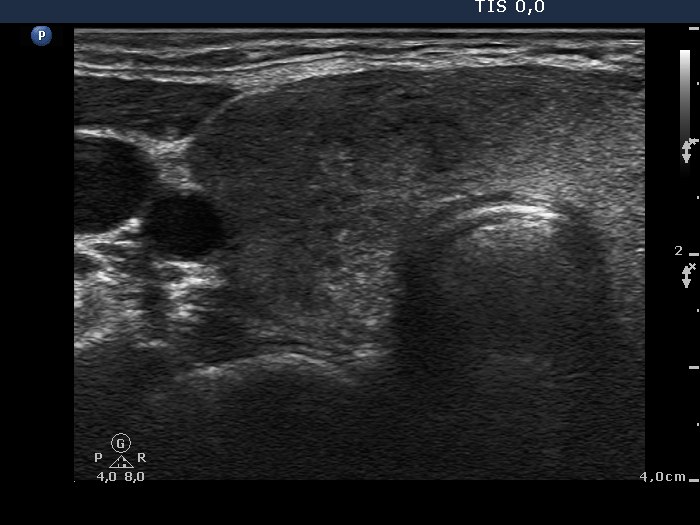

Ultrasonography: The right lobe was moderately hypoechogenic, while the left one was echonormal-minimally hypoechogenic. Several more hypoechogenic areas with ill-defined borders were found. The vascularization was decreased.